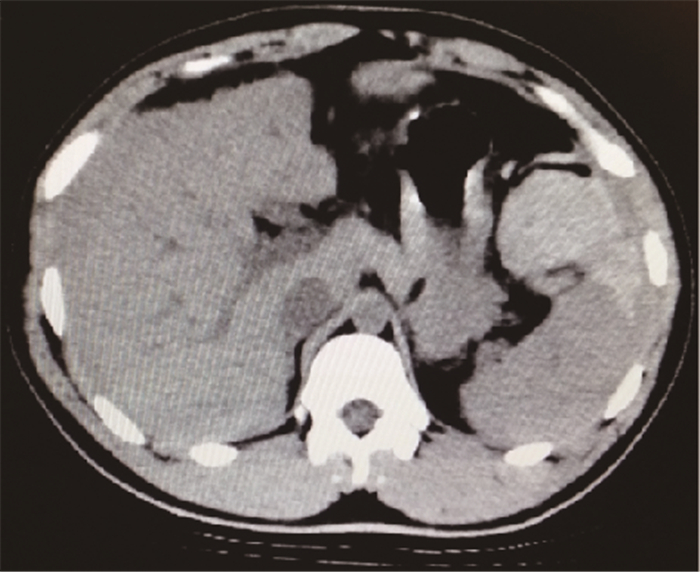

病例資料????患者,男,18歲,因腹部脹痛4 d由基層衛生院轉入我院。患者4 d前曾醉酒后劇烈嘔吐10多次,嘔吐物為胃內容物,無咖啡樣物。當晚開始出現腹部脹痛,以左中上腹明顯,伴頭暈、惡心、乏力,無發熱、畏寒,無氣促、呼吸困難,無腹瀉、血便。曾在當地衛生院“輸液”治療(用藥不詳),癥狀無好轉,并出現頭暈、心悸加重,血壓下降,隨即轉送我院急診就診。行腹部CT檢查后,門診擬“血腹查因,失血性休克”收外科住院。既往史無特殊,否認外傷史。體格檢查:體溫36.5℃,呼吸22次/min,脈搏114次/min,血壓80/56 mm Hg(1 mm Hg=0.133 kPa)。面色蒼白,心肺檢查未見異常,腹脹,以左中上腹明顯,全腹壓痛,伴輕度反跳痛和肌緊張。未觸及包塊,肝脾肋下未觸及,移動性濁音陽性,肝脾區無明顯叩痛,腸鳴音正常。實驗室檢查:血紅細胞2.12×1012/L,血紅蛋白65 g/L,血尿淀粉酶正常。影像學檢查:腹部CT示脾不大,密度未見異常,脾臟上極輪廓不清,周緣見新月形混雜液體密度影,脾胃間見團狀高密度影,肝外緣見弧形液性密度影,厚約2.1 cm(圖 1),盆腔見大量積血。左下腹腹腔穿刺抽出3 mL不凝血。隨即行剖腹探查,術中見脾胃韌帶撕裂出血,脾門附近見大量凝血塊,出血總量2 200 mL,探查腹腔內其他臟器未見異常,考慮出血為劇烈嘔吐致脾胃韌帶撕裂所致。患者術后10 d治愈出院。